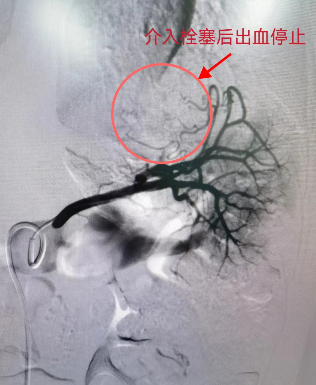

车祸骨折脾脏破裂 西安市红会医院多科室协作介入救治|骨病|栓塞|出血

9岁娃车祸骨折脾脏破裂 西安市红会医院多科室协作介入救治_患者_诊疗